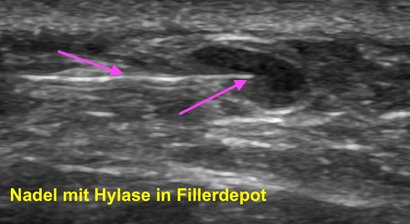

Ultraschallgezielte Ästhetik: Faltenunterspritzungen, Mini-Lifts und Volumenaufbau sowie Hylasebehandlungen

Sicherheit und Präzision durch exakte und zurückhaltende Injektionen von Botox und Hyaluronsäure-Filler sowie von Hylase, kontrolliert durch hochauflösenden Ultraschall - warum das sinnvoll ist (Stichwort: Vascular Mapping) und welche ästhetischen Behandlungen ich anbiete, finden Sie unter Leistungen.